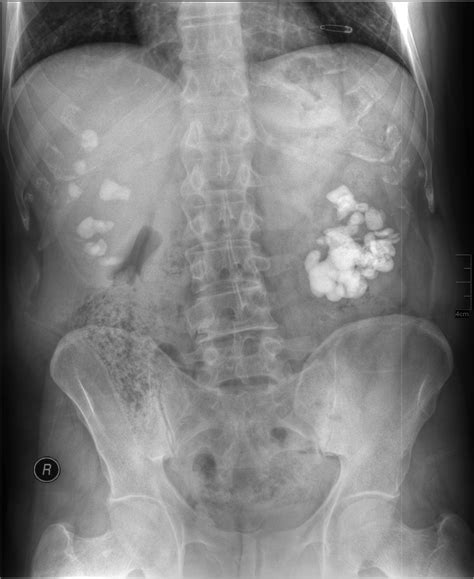

• Foreign objects, such as swallowed items or surgical instruments.

A Belly X Ray can help diagnose a wide range of conditions, including:

• Kidney Stones: Hard deposits that form in the kidneys and can cause severe pain and urinary tract infections.